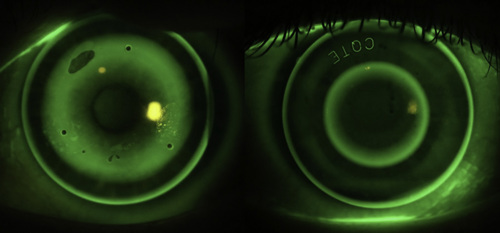

A comparison of orthoK lens designs. Left: An ‘adult’ orthokeratology lens (BE, Capricornia, AUS). BOZD >6mm, e=0. Right: A customised lens for myopia control (Eyespace Forge design, CLC, NZ) BOZD 5.5mm, e=0.99

When fitting an adult with ortho-k we want to minimise this paracentral steepening as it negatively affects vision due to spherical aberration and increased halos and glare at night when the pupil enlarges. Normal orthokeratology lenses tend to have a large spherical back-optic zone radius of 6mm or greater to facilitate this.

In the case of a rapidly progressing myopic 10-year-old this aberration is what we can use to prevent further eye growth. It’s also useful to remember that these patients tolerate aberration in their vision very well; they are not driving at night and are typically just pleased they can see their friends at the other end of the playground!

Lately most ortho-k experts around the world are using customised myopia control ortho-k lenses with the primary design consideration being to maximise the plus power of the peripheral pupillary zone. This typically involves smaller back optic zone diameters of 5-5.5mm (or smaller if the child has a small pupil) with aspheric base-curves. These lenses create a highly aspheric, small diameter treatment zone with a steeper paracentral ring. Amazingly vision is still great with these lens designs, in a similar way that centre-distance multifocal soft contact lenses are well tolerated by adults.